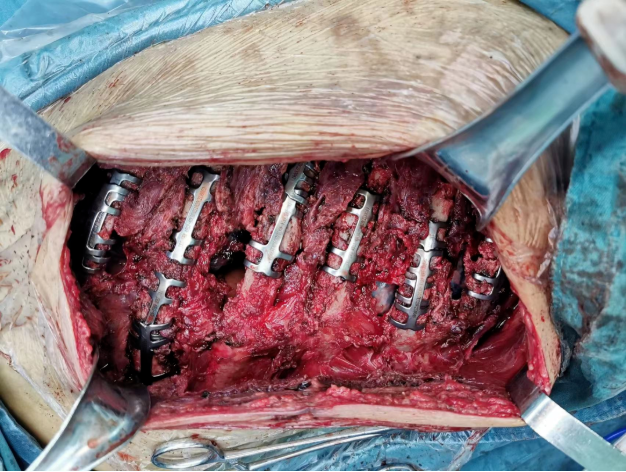

再经多学科反复会诊论证,手术指征明显。在患者带机17天后,胸心外科主任医师李德刚率团队为患者进行了“右胸廓重建成形术+右肺挫裂伤修补术”。

术中,探查可见右侧第3-9肋骨骨折,均错位明显,大部分骨折断端重叠、短缩,多处肋骨断端刺破胸膜,进入胸腔,还有肺组织嵌顿于骨折断端内。

手术历时3个多小时顺利完成。术后第七天,患者病情较前好转,顺利拔除气管插管,成功脱机,目前继续在院治疗。